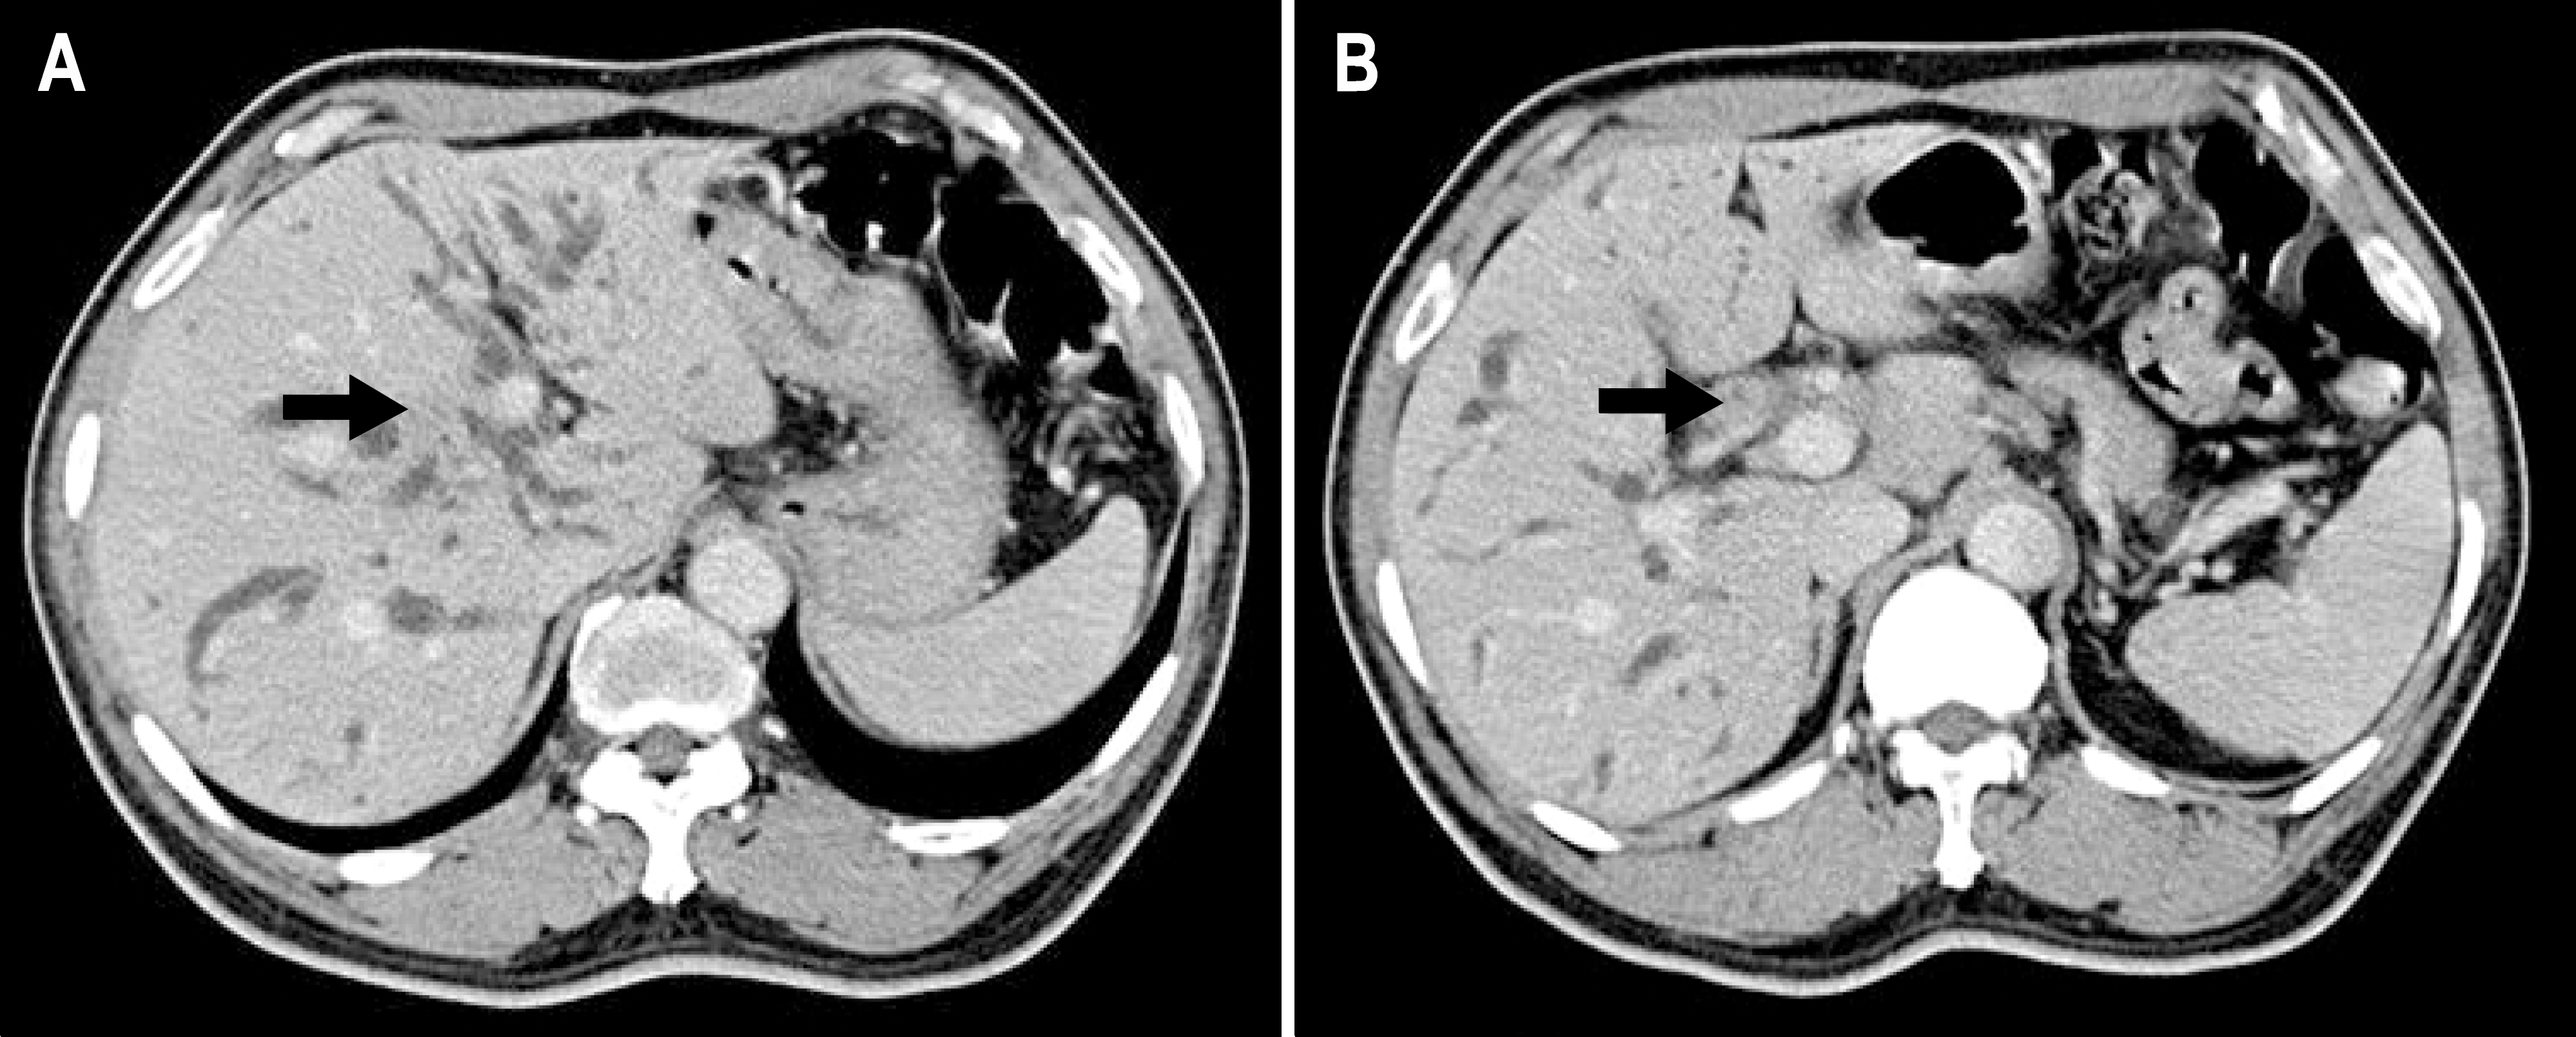

Fig. 1.

Axial contrast-enhanced CT scans during the portal venous phase showed bile duct wall thickening of hyperattenuation from right secondary confluences (arrow in A) to the proximal common hepatic duct (arrow in B), and diffuse dilatation of both intrahepatic bile ducts.